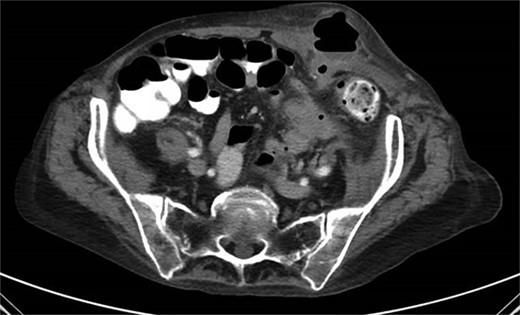

One month prior, the patient was admitted for complicated perforated sigmoid diverticulitis. Treatment included piperacillin-tazobactam (Zosyn), bowel rest, and fluid resuscitation. On hospital Day 6, her condition worsened with increased nausea, vomiting, and an elevated WBC count of 15. CT imaging revealed a 4.8 × 4.4 × 4.0 cm diverticular abscess, leading to CT-guided percutaneous drainage by interventional radiology (Figs 4–7). Cultures grew Citrobacter sedlakii and Enterococcus faecium vancomycin resistant Enteroccus (VRE), and treatment was adjusted to include Bactrim, followed by daptomycin and levofloxacin. The abscess resolved after 3 weeks, and the drain was removed before discharge. The patient was instructed to follow up with her surgeon and undergo a 6-week interval colonoscopy.

CT showing resolution of abscess with IR pigtail drain in place.